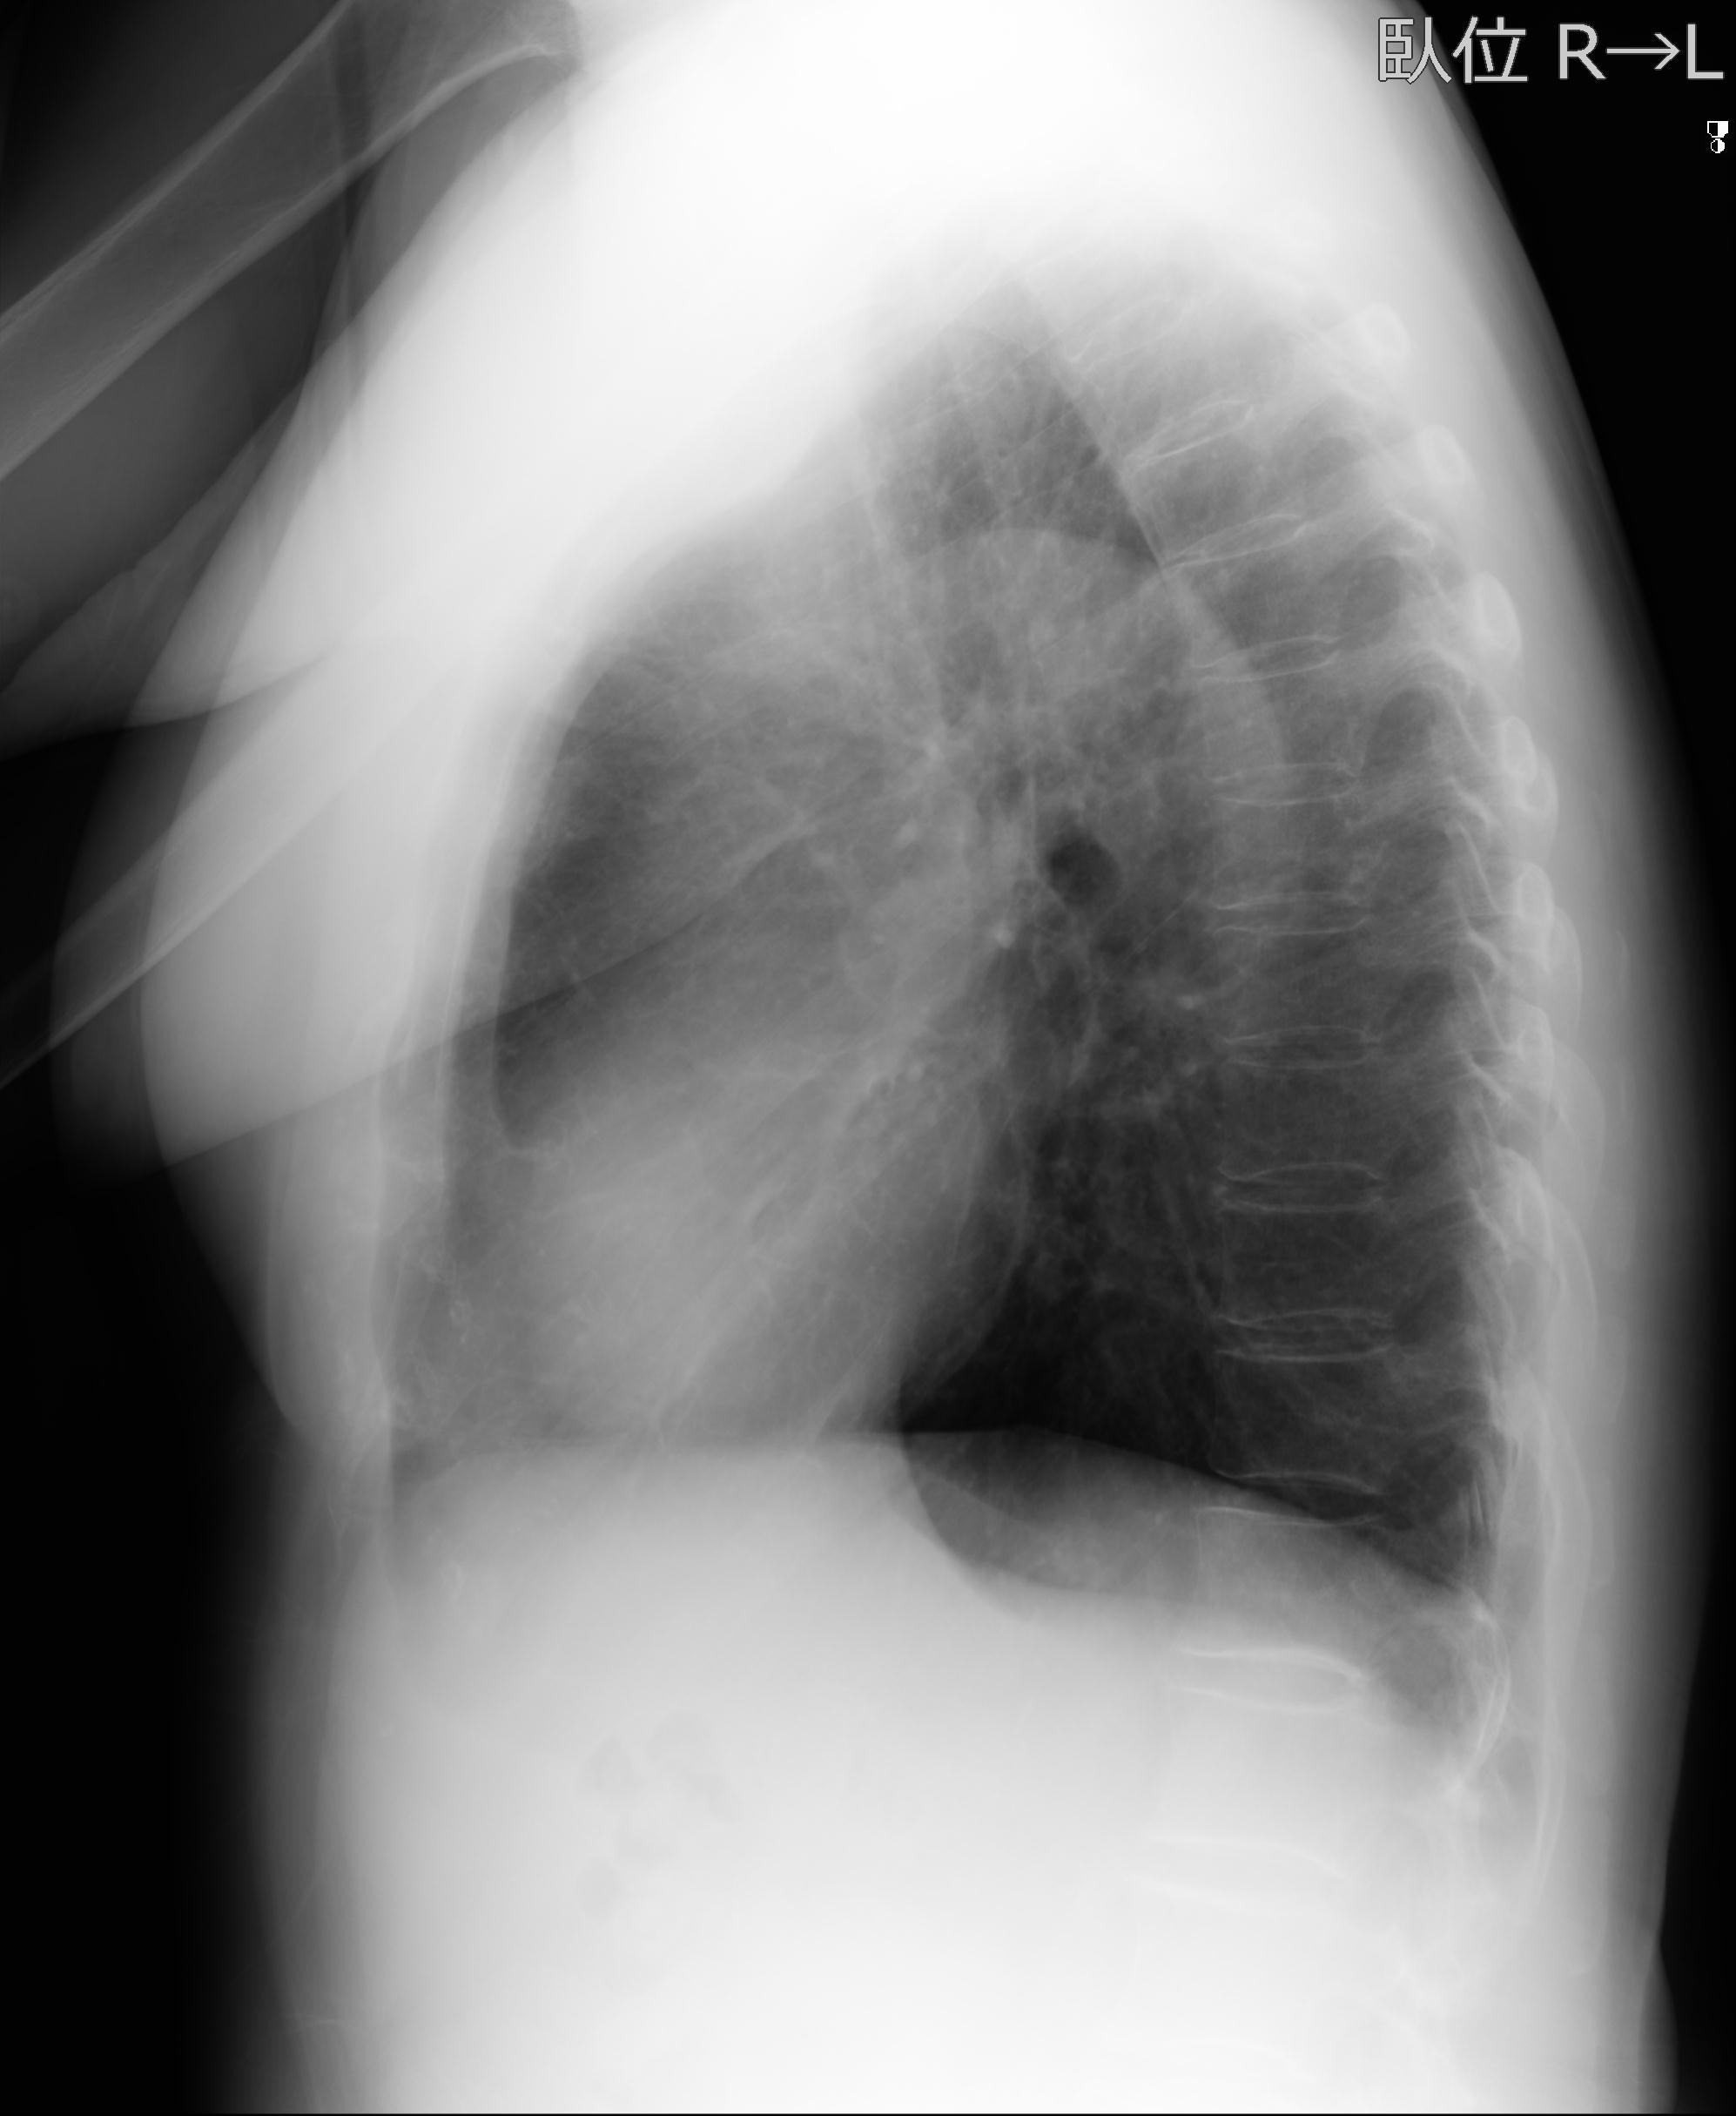

56476 8/28 4R 1/21 2R 左足関節 デジカメ写真 72歳女性 右足関節AS